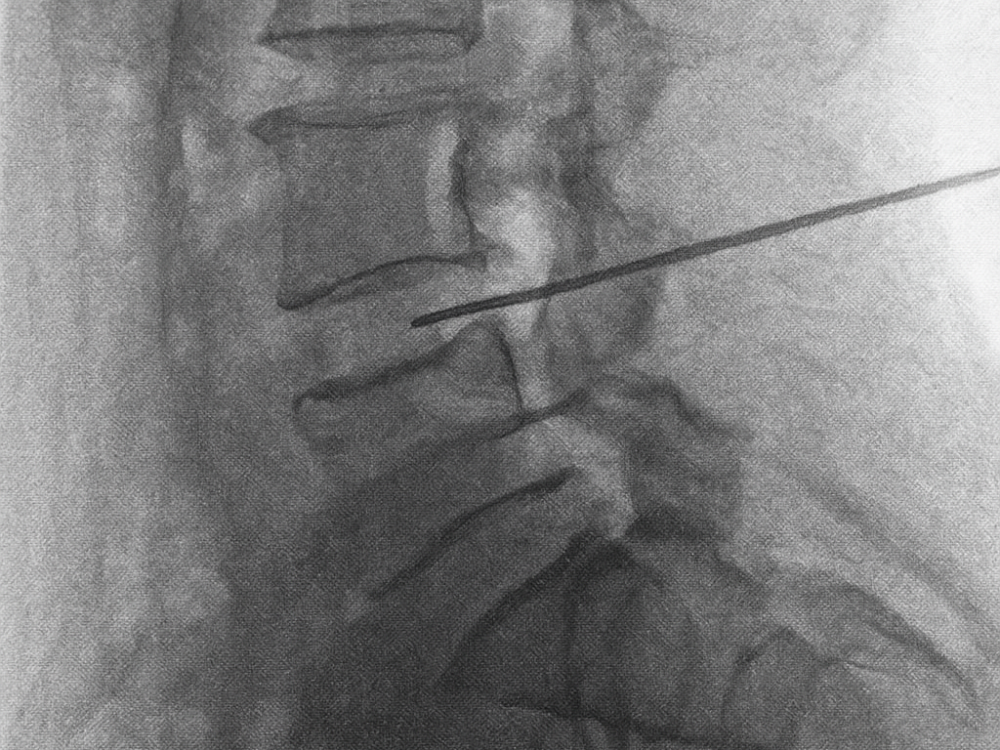

Discólisis con ozono

Tratamiento especializado que aplica ozono directamente en la zona afectada por hernia discal, logrando desinflamar, aliviar el dolor y evitar cirugía. Alternativa eficaz, ambulatoria y mínimamente invasiva.